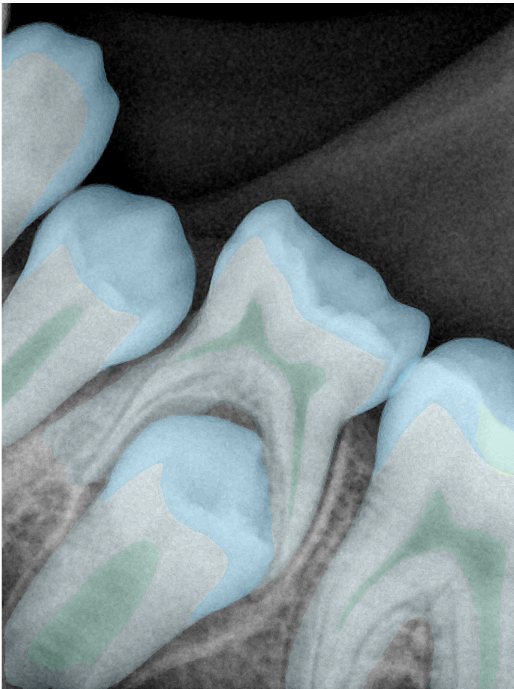

CR/DR 牙齿分割阶段记录

当前进展

- 完成了 CR/DR 牙齿相关分割训练

- 当前结果已经达到阶段预期,但仍有细节问题需要继续处理

相关测试

遇到的问题

- 训练过程中出现过 mask 下移问题

- 部分结果会出现 box 填充异常

- mask 边缘仍然有比较明显的锯齿感